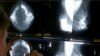

“Aunque me di cuenta temprano, estoy muy agradecida de no haber tenido que pasar por cosas mucho peores”, dijo satisfecha esta sobreviviente del cáncer de seno, quien hizo un llamado a las mujeres para que, cuando tengan sospechas, acudan rápidamente a su especialista y defiendan sus sensaciones pues, en su caso, en un principio no hubo detección alguna, pero ella insistió hasta practicarse una mamografía que le confirmó la enfermedad.